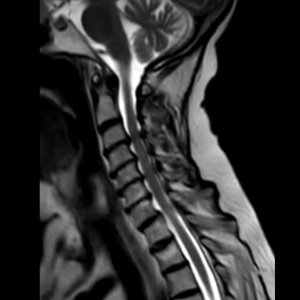

Spinal stenosis (Lumbar) Spinal stenosis (Cervical) Spinal stenosis (Thoracic) Lumbar Disc Herniation Spondylolisthesis Cervical Foraminal Stenosis Vertebroplasty Lumbar Fusion Anterior Cervical Fusion (ACDF) Posterior Cervical Fusion Thoracic Fusion Revision Lumbar Fusion Surgery Facet Joint Cyst Spinal Tumour Minimally Invasive Lumbar Fusion (XLIF) Minimally Invasive Lumbar Fusion (ALIF) Lumbar Fusion (TLIF) Thoraco-lumbar Fusion Lumbar Corpectomy Complex Lumbar Spine Surgery (Spino-pelvic fixation) Complex Cervical Spine Surgery Complex Thoracic Spine Surgery Occipito-cervical Fusion Minimally invasive surgery for thoracic disc herniation Other Related Topics